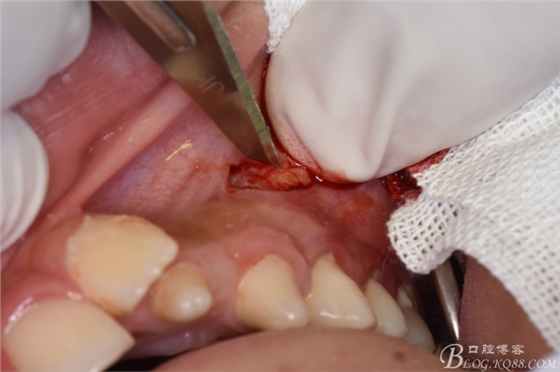

圖9.翻瓣、暴露出骨面

圖10.去骨

圖11.骨鑿去骨